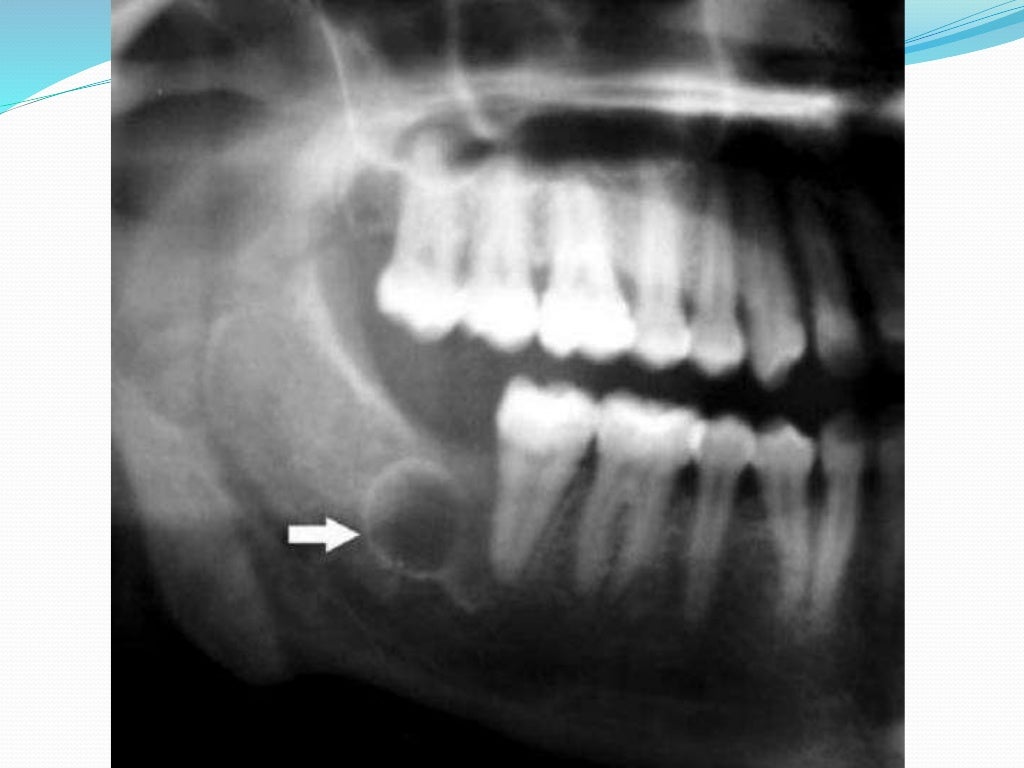

How can we diagnose and treat osteomyelitis of the jaws as early as Jaw Bone Sequestrum  Spontaneous oral ulceration with bone sequestration is a distinct lesion that most often presents over the prominence of the mylohyoid. Osteonecrosis of the jaw is characterized by formation of sequestrum which is a fragment of avital bone separated from adjacent. Spontaneous oral ulceration with bone sequestration is a distinct lesion that most often presents over the prominence of the mylohyoid. Jaw Bone Sequestrum.

From radiologypics.com

Clinical and panoramic radiographic features of osteomyelitis of the Jaw Bone Sequestrum  Spontaneous oral ulceration with bone sequestration is a distinct lesion that most often presents over the prominence of the mylohyoid ridge. Spontaneous oral ulceration with bone sequestration is a distinct lesion that most often presents over the prominence of the mylohyoid ridge. It is currently an uncommon entity (0.02%), but this could well. Osteonecrosis of the jaw is characterized by. Jaw Bone Sequestrum.

From www.researchgate.net